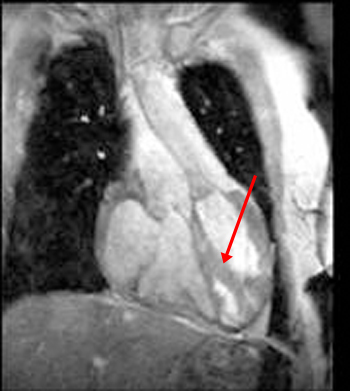

This gradient echo cine image in the coronal plane shows the great vessels arising in a parallel fashion, a finding that represents transposition of the great arteries (TGA). Notice that the ventricle on the patient's left is markedly trabeculated and a moderator band (arrow) is present; this therefore represents the morphologic right ventricle. In L-TGA , the morphological right ventricle is located in the usual location of the left ventricle and gives rise to the aorta. This configuration is also known a congenitally corrected transposition.